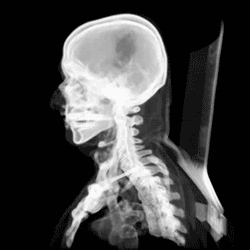

At birth, the human skull is made up of 44 separate bony elements. During development, many of these bony elements gradually fuse together into solid bone (for example, the frontal bone). The bones of the roof of the skull are initially separated by regions of dense connective tissue called fontanelles. There are six fontanelles: one anterior (or frontal), one posterior (or occipital), two sphenoid (or anterolateral), and two mastoid (or posterolateral). At birth, these regions are fibrous and moveable, necessary for birth and later growth. This growth can put a large amount of tension on the "obstetrical hinge", which is where the squamous and lateral parts of the occipital bone meet. A possible complication of this tension is rupture of the great cerebral vein. As growth and ossification progress, the connective tissue of the fontanelles is invaded and replaced by bone creating sutures. The five sutures are the two squamous sutures, one coronal, one lambdoid, and one sagittal suture. The posterior fontanelle usually closes by eight weeks, but the anterior fontanel can remain open up to eighteen months. The anterior fontanelle is located at the junction of the frontal and parietal bones; it is a "soft spot" on a baby's forehead. Careful observation will show that you can count a baby's heart rate by observing the pulse pulsing softly through the anterior fontanelle.